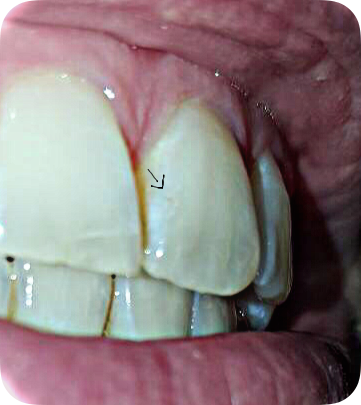

Ik heb er al jaren barsten in........ volgens de tandarts is dat het glazuur. Maar ik zag vandaag in de spiegel dat er een stukje uit mijn voortand is.

Ik heb er al jaren barsten in........ volgens de tandarts is dat het glazuur. Maar ik zag vandaag in de spiegel dat er een stukje uit mijn voortand is.